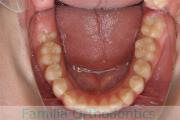

No.23V-308

- 主な症状:

- 欠損歯

- その他の症状:

- 空隙歯列

- 年齢:

- 17歳

- 性別:

- 女性

- 抜歯部位

- 上:

- 22欠

- 主な使用装置:

- Invisalign

- 治療にかかった費用:

- 88万円

永久歯がない為、隙間を埋めたいとのことで来院されました。検査診断を行ったところ、上の側切歯が左右とも欠損しているものの、矯正で歯を動かして隙間をすめて埋めるのは無理があるという判断になり、左上の乳歯は保存したまま、スペースは全て右上に集めました。マウスピース型矯正装置のひとつ、インビザライン/Invisalign®(薬機法および医薬品副作用被害救済制度の対象外)を使用しています。

歯の移動後に、右上にインプラントを埋め込む予定ですが、まだ若年のため、人工歯を接着剤とワイヤーで固定しています。